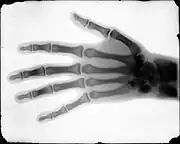

X-ray of the hand of Dr. Tennant taken by Buckwalter

In 1895, Buckwalter took interest in X-ray technology, after its discovery by professor Wilhelm Röntgen earlier that year. Sponsored by the Rocky Mountain News, Buckwalter partnered with physician C. E. Tennant and the Homeopathic Medical College of Denver on a series of X-ray photograph experiments. For the experiment Buckwalter produced X-ray tubes locally using leaded glass which was previously thought to be unsuitable, but the experiment proved that leaded tubes could produce a clear image.[6] The X-ray images were the first produced in the American West and among the earliest in the country.[1][7]

After the Rocky Mountain News published the results of the experiment, Buckwalter and Tennant were contacted by attorneys Ben Lindsey and Fred W. Parks to examine a client in a malpractice lawsuit with the new technology. The lawsuit represented James Smith, who had fractured his leg after falling from a ladder. He was examined by Dr. W.W. Grant, who misdiagnosed the fracture, insisting the leg was merely stiff. Instead of immobilizing the limb he prescribed exercises which exacerbated the injury. Case number 24159 was heard in the District Court of Arapahoe County (now Denver) on December 2, 1896, by Judge Owen Le Fevre, who allowed Buckwalter and Tennant to testify as expert witnesses and present their findings. The defense objected unsuccessfully to the court, arguing X-rays were the "testimony of a ghost". The X-rays along with the testimony of Buckwalter and Tennant proved that there was a fracture in the leg. The landmark case marked the first time that X-ray evidence was admitted into a court of law.[8]